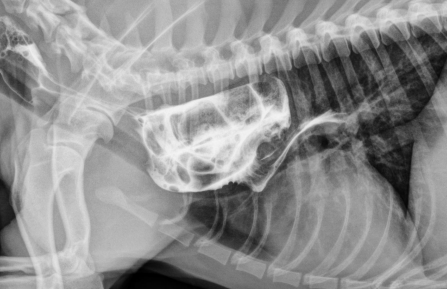

Gastric Dilatation-Volvulus (GDV)

Et: pylorus moves R → ventral → L → dorsal

mucosal damage, sepsis, portal vein obx + hypertension, vena cava obx, poor cardiac output

Sig: Deep-chested, Lg breeds, older, once-daily feeding, genetics, stress, exercise after eating

Cs: Retching, pain, distended abdomen, hypersalivation, VPC, shock, splenic congestion (often corrects on its own), hypoxia, acidosis, death

Dt: lactate trends, ECG (VPC), PT/PTT, RL rads w/ double bubble

Tx: gastric decompress (Trocarization, OG tube), right gastropexy, de-rotation, tube feed, famotidine, pantoprazole, mu opioids, fluids, O2

** Stand on left side, R hand pylorus, L hand on top of fundus - then rotate **

Tx arrythmias if: V tach >160-180. R on T, multifocal, pulse deficits

Emergency but good prognosis

NO NSAIDS or medical management